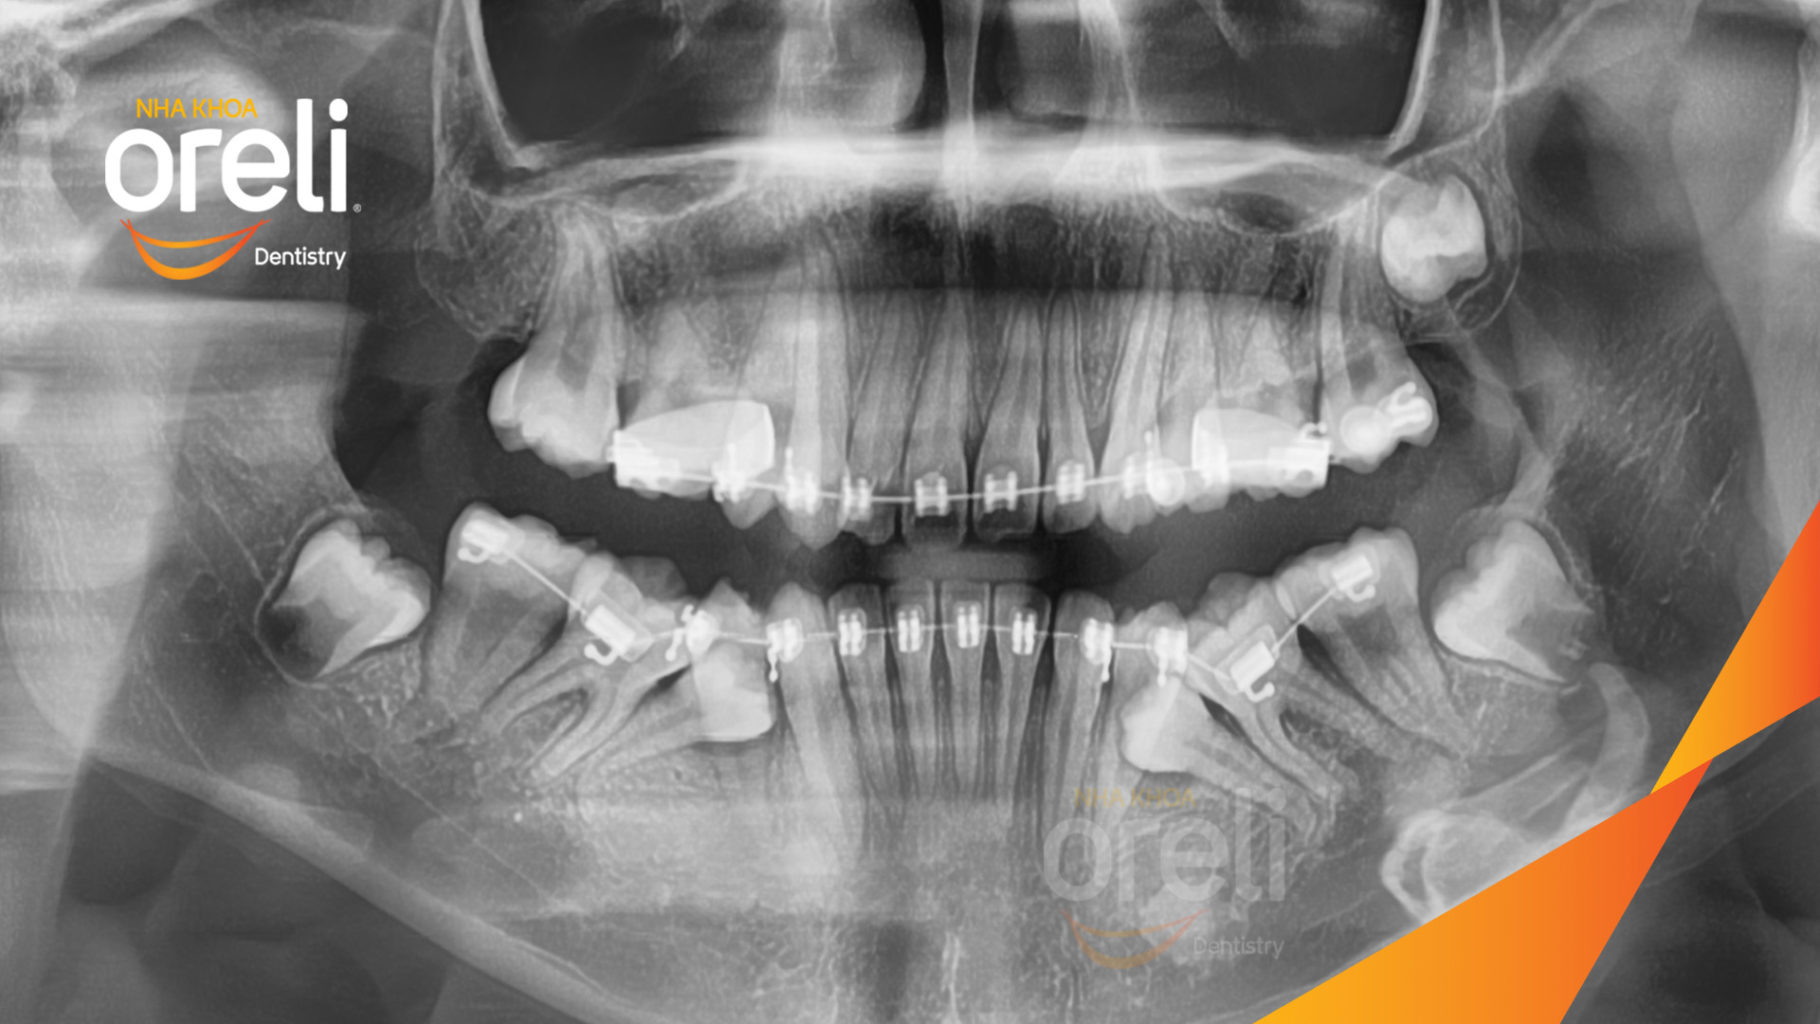

Ca niềng chỉnh chen chúc hẹp hàm nặng cả trên và dưới – Kết quả điều trị thực tế tại nha khoa Oreli

Ca niềng răng chen chúc phục hồi ăn nhai và thẩm mỹ nụ cười. Kết quả thực tế trước và sau điều trị tại Nha khoa Oreli.

Hình ảnh thực tế